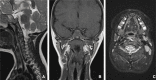

Figure 3. Sagittal T2-weighted (A), coronal T1-weighted (B) and axial T2-weighted with fat saturation (C) planes of the head and neck MRI.

(A) Cranial portion of the foreign body (orange arrow) perforating the left longus colli muscle associated with high intensity T2-weighted changes within the muscle; (B) Right extremity of the foreign body (orange arrow); (C) Infiltration and thickening of the left longus colli muscle near to the foreign body (orange arrow).